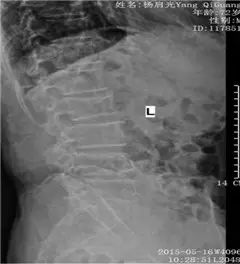

DR正侧位:腰椎退变